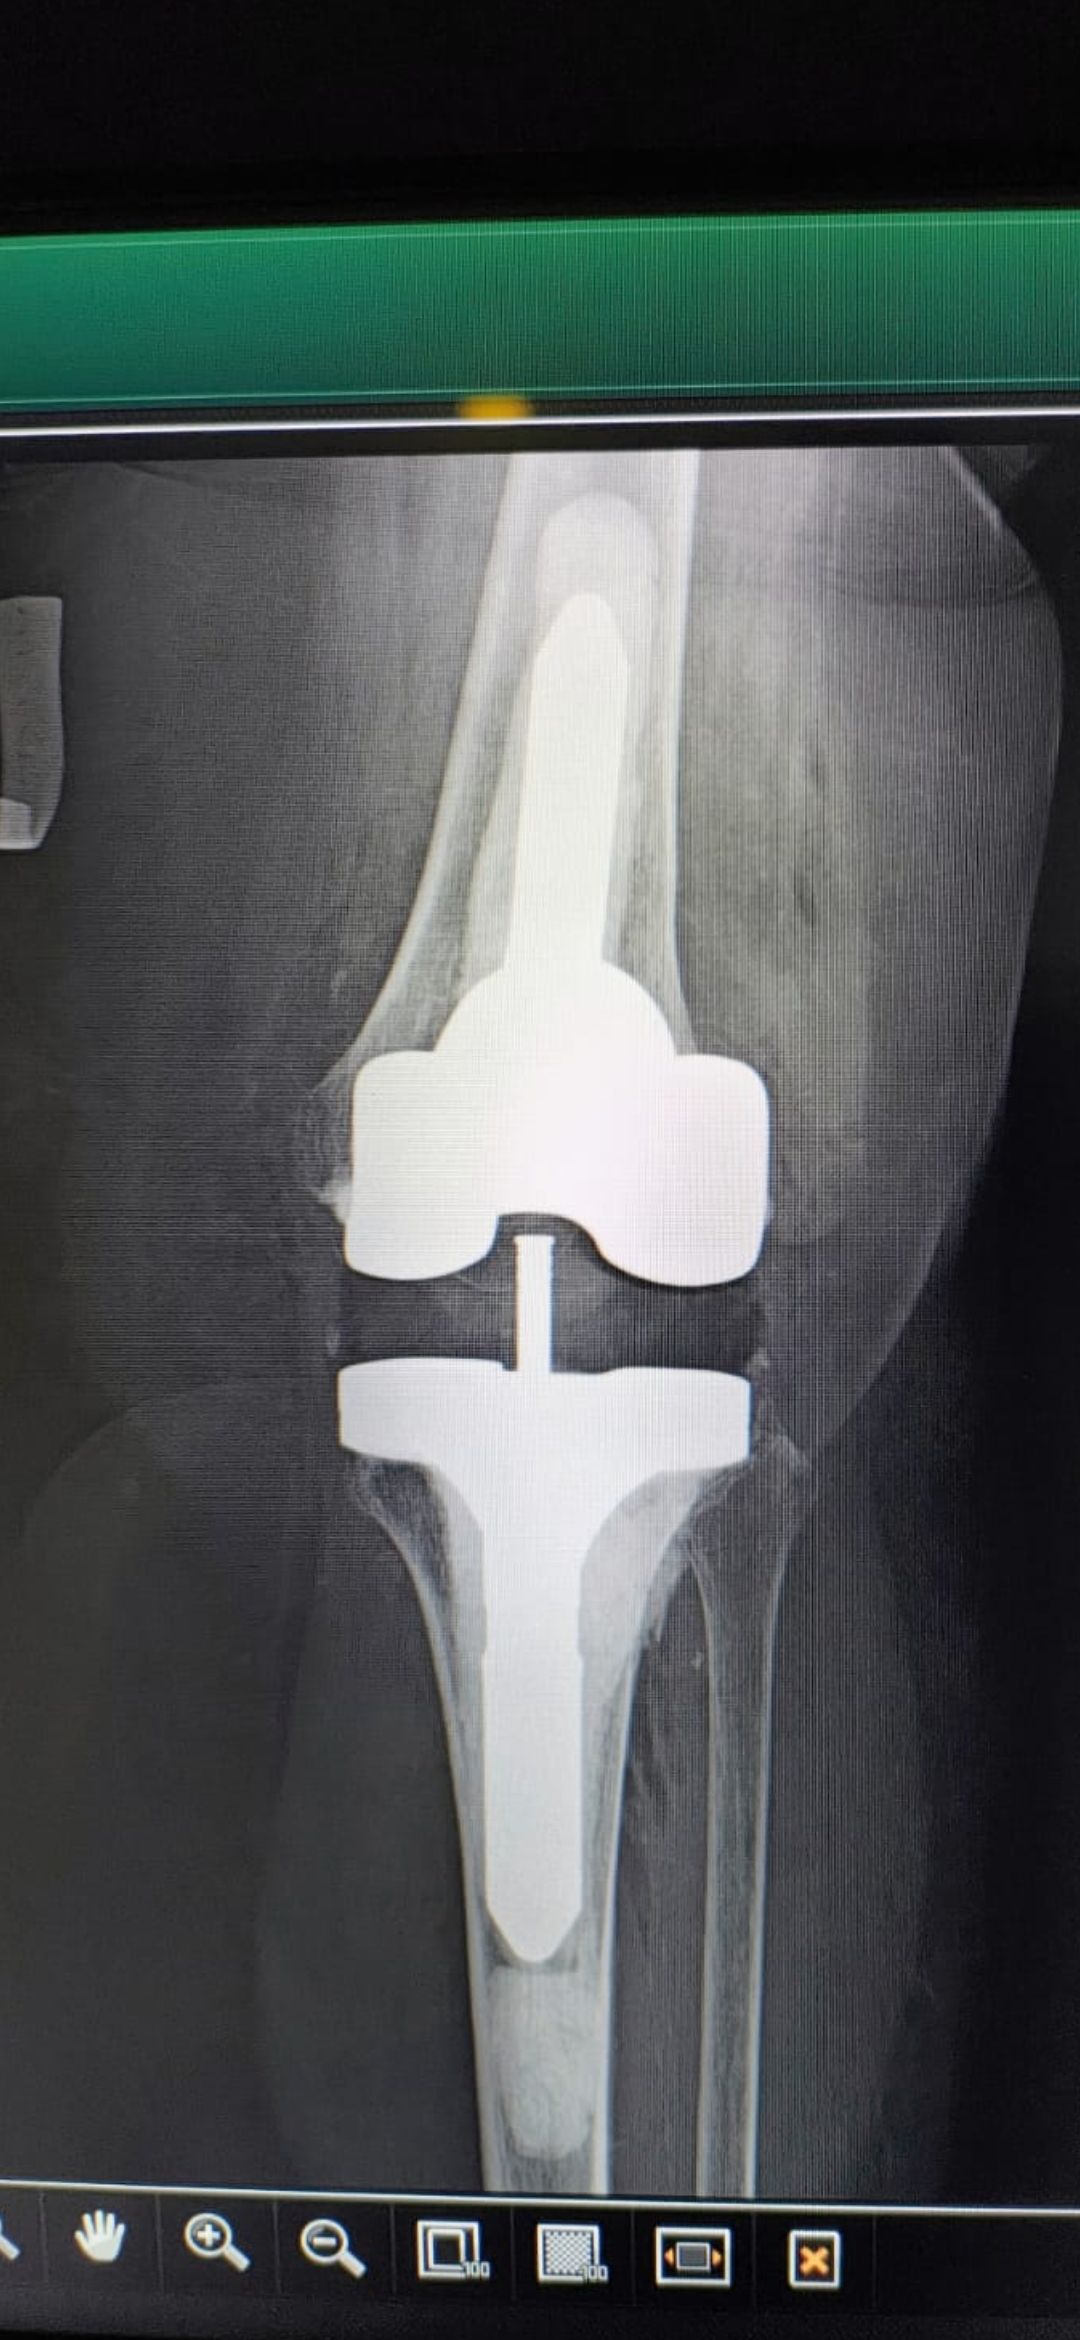

Soy   egresado  de  la  Universidad Autonoma de   Nuevo  Leon. especialidad de ortopedia y traumatologia  en    hospital  numero  21  del  IMSS ne Monterrey  N.L ,con entrenamiento en la  subespecialidad  de   reconstrucion  articular  y  artroscopia  que incluye  lesiones  de  meniscos  , reconstruccion de ligamentos cruzados , lesiones  condrales ,  gonartrosis   tengo  una  historia laboral    institucional de 30  años    hasta el 30  de lulio del 2024 estuve  10  años  en  el  modulo  de  artroscopia  con aproximadamente   1120    artroscopias  de rodilla   y  15 años  en  el  departamento  de    artroplastia  de rodilla  o  de  reemplazos  articulares   ,  los  ultimos   15  años    como profesor  adjunto   y titular  en los cursos    de pre  y posgrados  de  traumatologos  en la  subespecialidad  de  con aproximadamente   160 cirugias  institucionales    en   artroplastia de  rodilla    por  cada año   y  un  numero menor en el  medio particular  dando un total  aproximado  de  2,560  cirugias . de  estas  el  10%    de  revision  y  5%  preotesis    tumorales    de  actualmente   en  funciones  en  el  medio privado  y  acreditado  en todos los  hospitales  de la  localidad  y  con todas  las  aseguradoras   de  gastos  medicos .